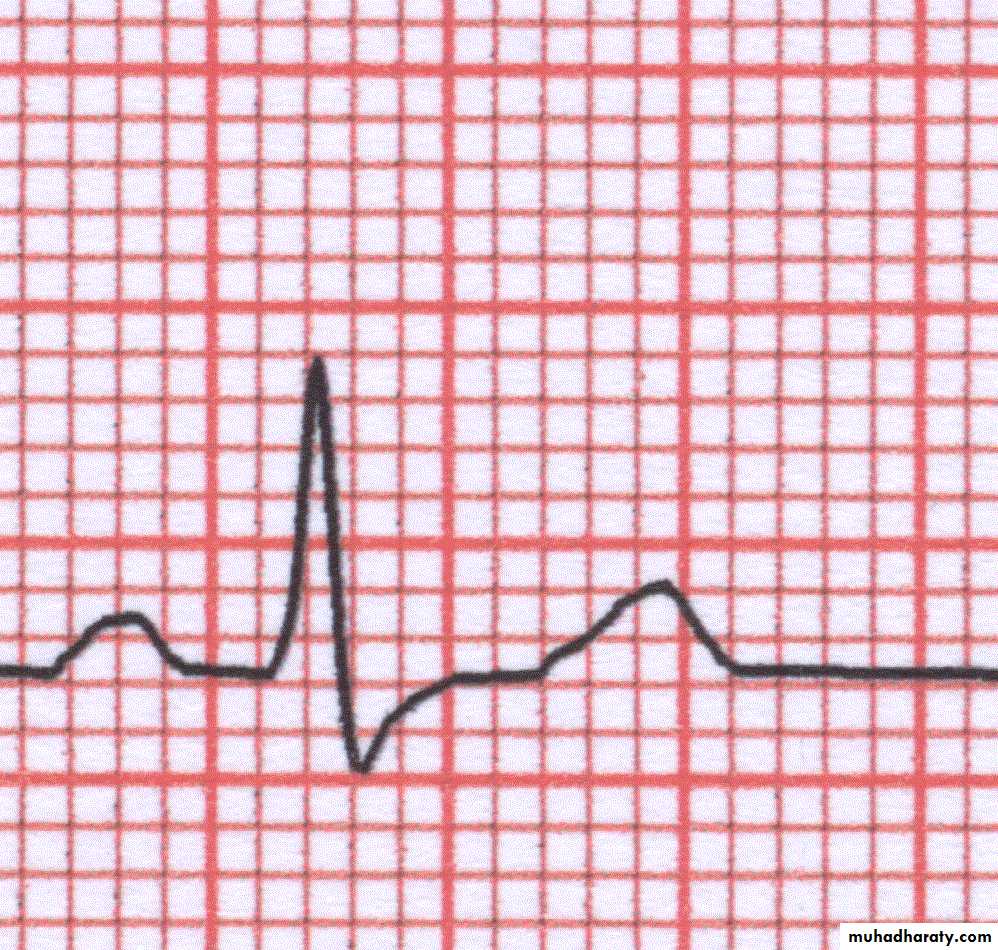

ECG wave

ECG wave(cont.)

T wave

Normal T wave is asymmetrical, first half having a gradual slope than the secondShould be at least 1/8 but less than 2/3 of the amplitude of the R

T wave amplitude rarely exceeds 10 mmAbnormal T waves are symmetrical, tall, peaked, biphasic or inverted.

T wave follows the direction of the QRS deflection.T wave